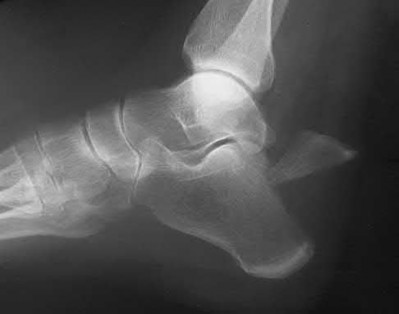

2. # A 35-year-old woman is involved in a head-on collision while driving. Initial radiographs are shown in Figures 8a and 8b. Injury to what vessel increases the risk for osteonecrosis of the injured bone?

5. Artery of the tarsal sinus Corrent answer: 4

The patient has a Hawkins type III talar neck fracture-dislocation with a risk of osteonecrosis ranging from 69% to 100%. Anatomic studies have shown that the artery of the tarsal canal supplies the lateral two thirds of the talar body.

The other vessels listed provide no significant contribution to the talus.